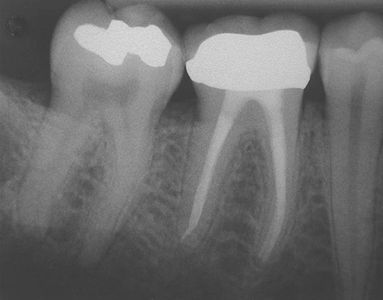

When decay or cavities are left untreated for a long period of time, the nerve tissue of a tooth can become infected resulting in severe pain. In this case, root canal treatments are usually indicated. Root canal treatments involve removing infected tissues and cleaning out the inside of the tooth all the way down the roots using various different dental materials and tools. A permanent filling material would be placed to seal the canal to prevent future infection

Over time, teeth with large fillings or root canal-treated teeth often become brittle and are more susceptible to breakage and fractures. Dental crowns or more familiarly known as “caps” can be placed over a tooth to restore its shape and size, strength, and to improve its appearance.